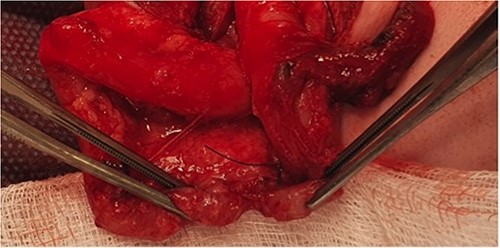

A female infant born at 37 weeks (birth weight 1.9 kg) and a neonatal course complicated by significant respiratory distress and bilateral pneumothoraces, also found to have a hypoplastic aortic arch on echocardiogram. On day 4 of life, she underwent an aortic arch repair (bypass time - 2 h 44 min, clamp time 24 min) and the chest was left open. Inotropes were required post operatively (3 days of vasopressin, 4 days of dopamine, and 19 days of milrinone). At 4 weeks of age, she underwent chest closure. At 5 weeks of age, she developed feed intolerance, abdominal distension, and bilious nasogastric aspirates. She was treated with bowel rest and intravenous antibiotics for 1 week. At 9 weeks of age, she was investigated for ongoing inability to advance feed and found to have distal transverse colonic obstruction (Fig. 4). At laparoscopy, a dilated proximal transverse colon was encountered with a clear transition point to collapsed distal colon. However, the serosal surface was intact and uninterrupted. An enterotomy made at the transition point revealing complete occlusion of the lumen by a mucosal web consistent with an acquired colonic atresia. A transverse loop colostomy was fashioned at this point and the baby recovered well. She is awaiting colostomy closure. A diagnosis of Turner’s syndrome was later confirmed. We have included a summary of cases 1, 2, and 3 in Table 1.

Contrast enema for case 3 showing complete failure of passage of contrast into distal transverse colon.